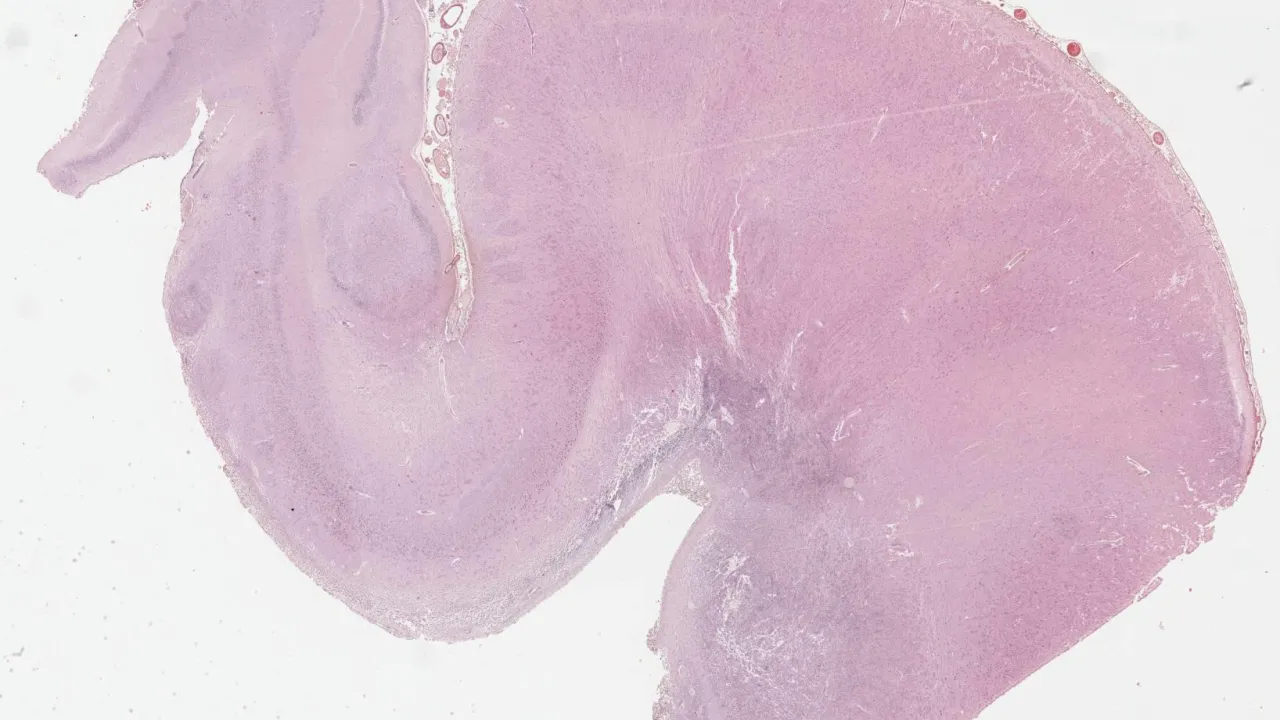

Brain, Adamantinomatous craniopharyngioma